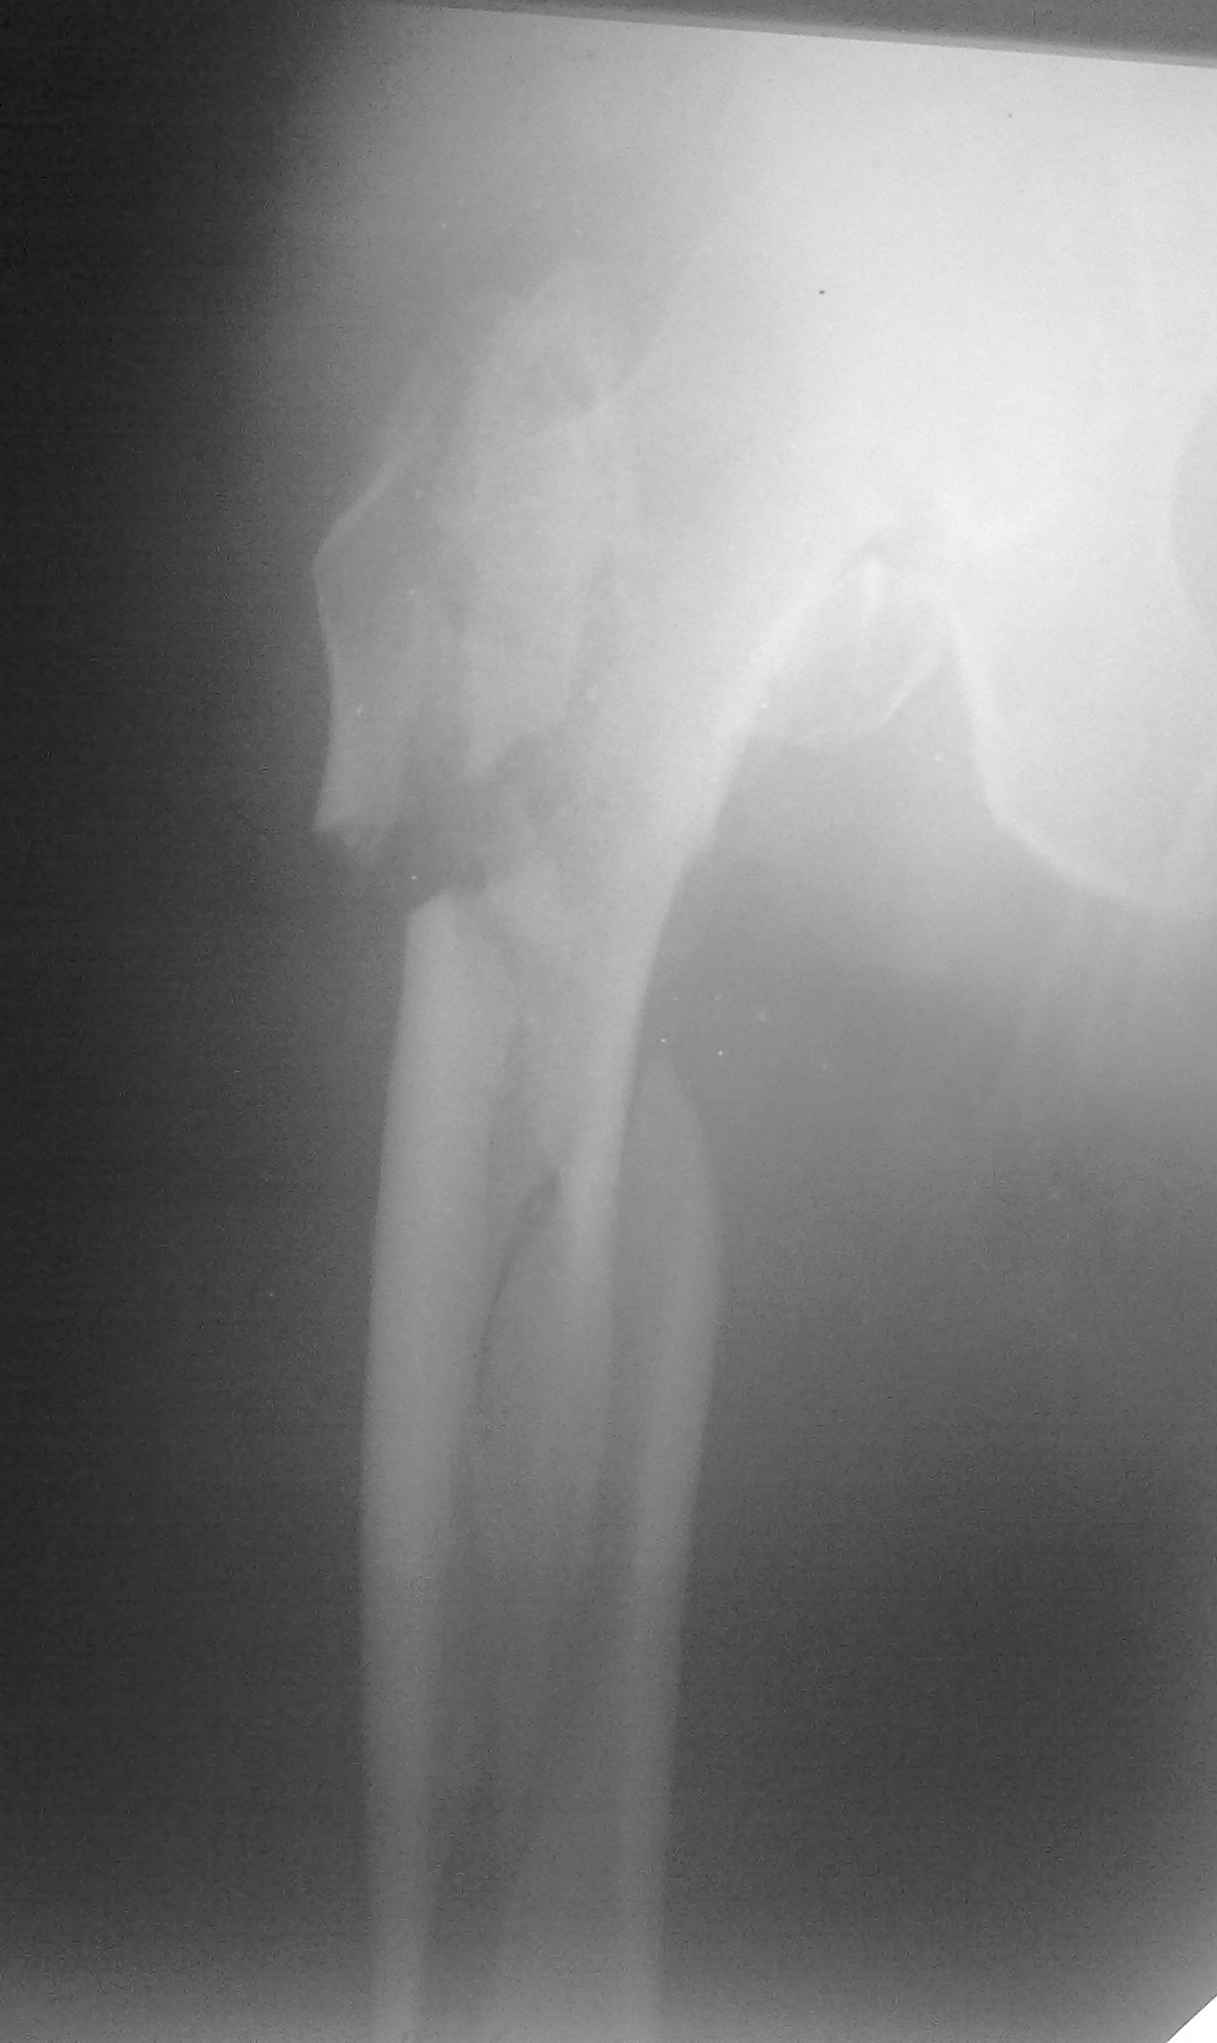

Пациент 83 года. Реконструктивный бедренный стержень Chm

Вложение не в текстовом формате было извлечено…

Имя     : 29092009071.jpg

Тип     : image/jpeg

Размер  : 43203 байтов

Url     : http://weborto.net:8080/pipermail/ortho/attachments/20101106/4466bdf3/attachment-0006.jpg